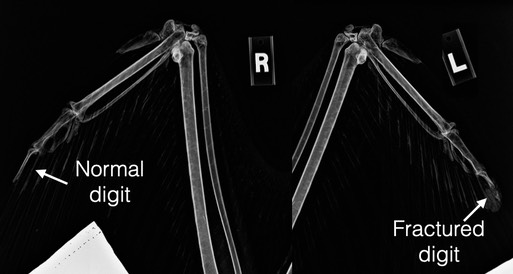

Bald Eagle 23-024 is being treated for lead toxicity. The eagle was found near Baker City and transported to BMW by Oregon Department of Fish & Wildlife. In addition to having a blood lead level of 52 micrograms/deciliter (20 mcg/dl is considered toxic), the eagle has fractures in his left wingtip and left halux (backward pointing toe). He seems to be responding well to chelation to remove the lead from his blood. We will have to see how the fractures affect his ability to maneuver in flight and grasp prey with his left foot.